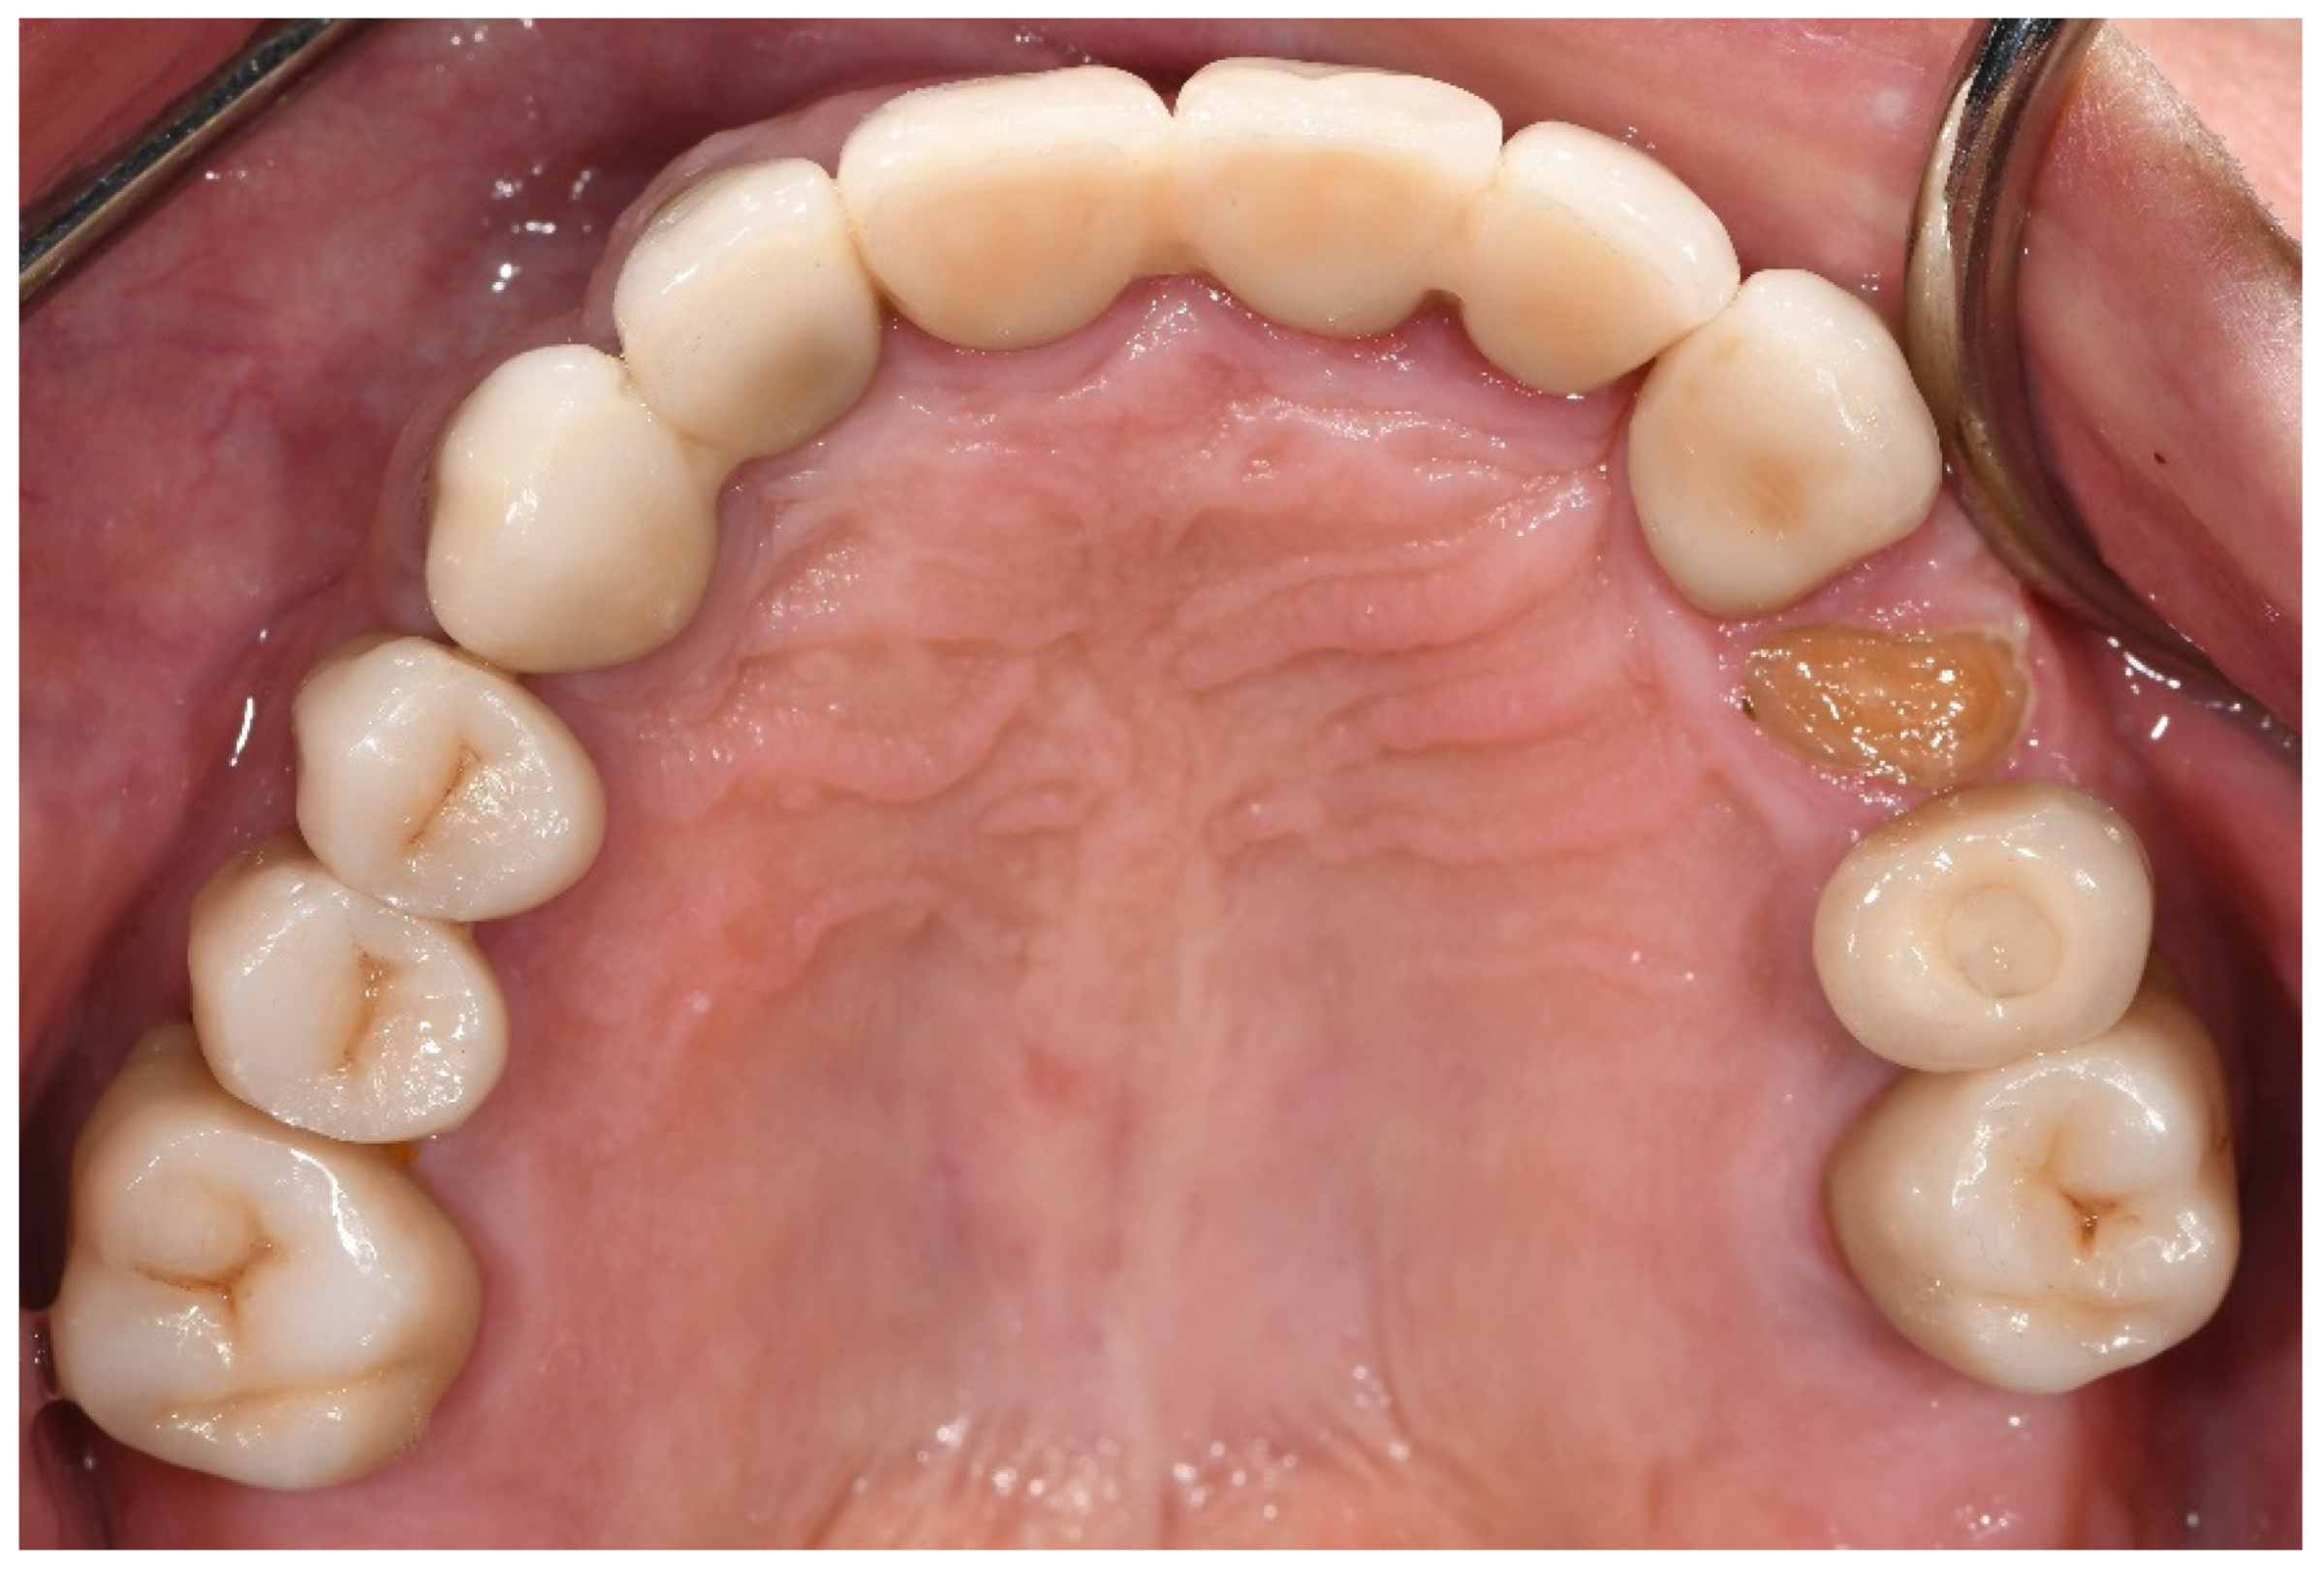

With regard to biological complications, the only complications that exhibited a borderline, although not significant, difference were three fractured teeth exclusively in the bruxer group (p = 0.051). The fractured teeth were in two different patients; one patient with two vital fractured premolars (first tooth after one year of function, the second after four years, Figure 1), and one patient with a non-vital fractured canine (after five years of function). Both patients did not wear an occlusal guard.

Figure 1. Patient with a fractured upper first pre-molar four years post-cementation. Three years prior, the same patient experienced fracture in an upper second pre-molar, which was replaced with a screw-retained implant restoration.